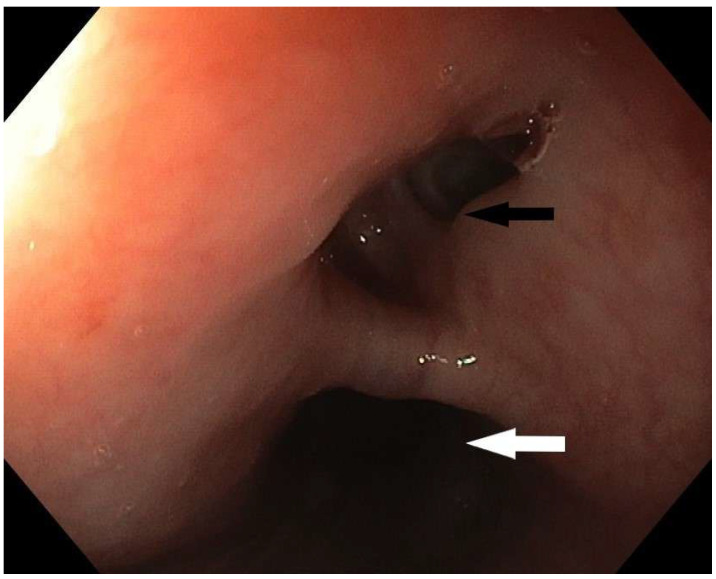

气消化瘘管是临床实践中的一个主要挑战。尽管最近内镜腔内修复技术有了很大的优势,但这个问题的发病率和死亡率都很高。特殊的问题是瘘管局部较高,累及食管和气管近端,这在成人中最常由插管后损伤引起。手术通常要求很高,而且是为那些其他侵入性较小的选择失败的患者保留的。在此,我们报告一例插管后气管食管瘘,经内镜血管塞置入成功治疗。

Aerodigestive fistulas represent a major challenge in clinical practice. This problem is burdened with severe morbidity and mortality, despite recent advantages in endoscopic endoluminal repair techniques. Special problems are fistulas localized higher, engaging the proximal esophagus and trachea, which in adults most often result from post-intubation injury. Surgery is generally demanding and reserved for the patients in whom other, less invasive options fail. Hereby, we present a case of post-intubation tracheoesophageal fistula, successfully treated with endoscopic vascular plug placement.